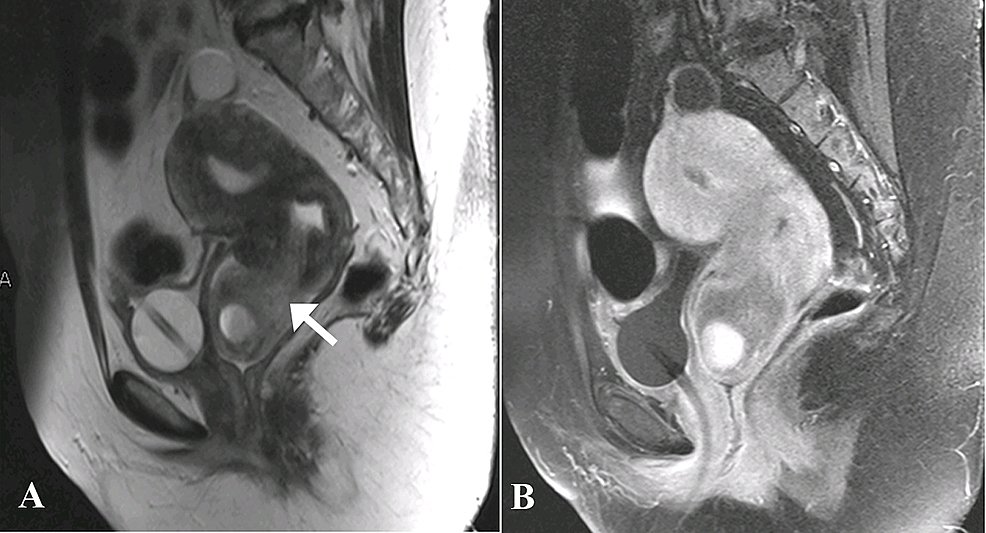

Magnetic resonance imaging (MRI) of the pelvis with contrast was then done which demonstrated a large, well-defined abnormal signal intensity polypoidal mass distending the endocervical canal and extending through the external os (external orifice) into the upper one-third of the vagina. It was measuring 46 x 46 x 58 mm in maximum dimensions. It appeared to be connected to the uterine endometrium by a T2-hypointense stalk seen within the endometrial cavity. No evidence of invasion into adjacent structures was seen. The uterine junctional zone was also thickened and ill-defined, which was suggestive of adenomyosis. The lesion contained rounded T1-hyperintense cystic spaces with fluid-fluid level within it, suggestive of hemorrhages. The lesion did not show significant diffusion restriction, and enhanced heterogeneously in the post-contrast study. Post-contrast enhancement was relatively less than that of myometrium (Figures 3-5).

On ultrasound, polypoid adenomyomas can appear as solid, well-circumscribed endometrial masses with cystic areas [2]. On MRI, they are found to be well-defined intracavitary uterine masses and may involve the lower uterine segment, endocervix or uterine corpus. On T1-weighted images they are usually isointense. Signal intensity on T2-weighted images may depend on the size and amount of glands within the tumor. The presence of a visible stalk passing through the cervix and connecting a prolapsed mass back to the uterus is a helpful imaging finding that is often best appreciated at MRI and indicates a prolapsed uterine tumor, as seen in our patient. The stalk connecting an apparent cervical mass to the endometrial cavity, seen on MR imaging, is referred to the broccoli sign [7]. Some of these tumors may also show hemorrhage within the cystic spaces, which appear as hyperintense foci on T1-weighted images and are not suppressed on fat-suppressed T1-weighted imaging [8].

Therefore, hemorrhagic cystic spaces in a prolapsed uterine tumor are suggestive of a diagnosis of typical polypoid adenomyoma, especially in a premenopausal female with additional findings suggestive of adenomyosis as seen in our case. Blood-containing cystic spaces would be infrequently seen in leiomyomas and malignancy, although potentially can be seen in the setting of leiomyomas with red degeneration and in uterine sarcomas [9]. The enhancement pattern of polypoid adenomyomas is said to be irregular/heterogeneous. Diagnosing polypoid adenomyoma is essential because it may be managed by hysteroscopic resection, unlike an ordinary form of adenomyosis [10].